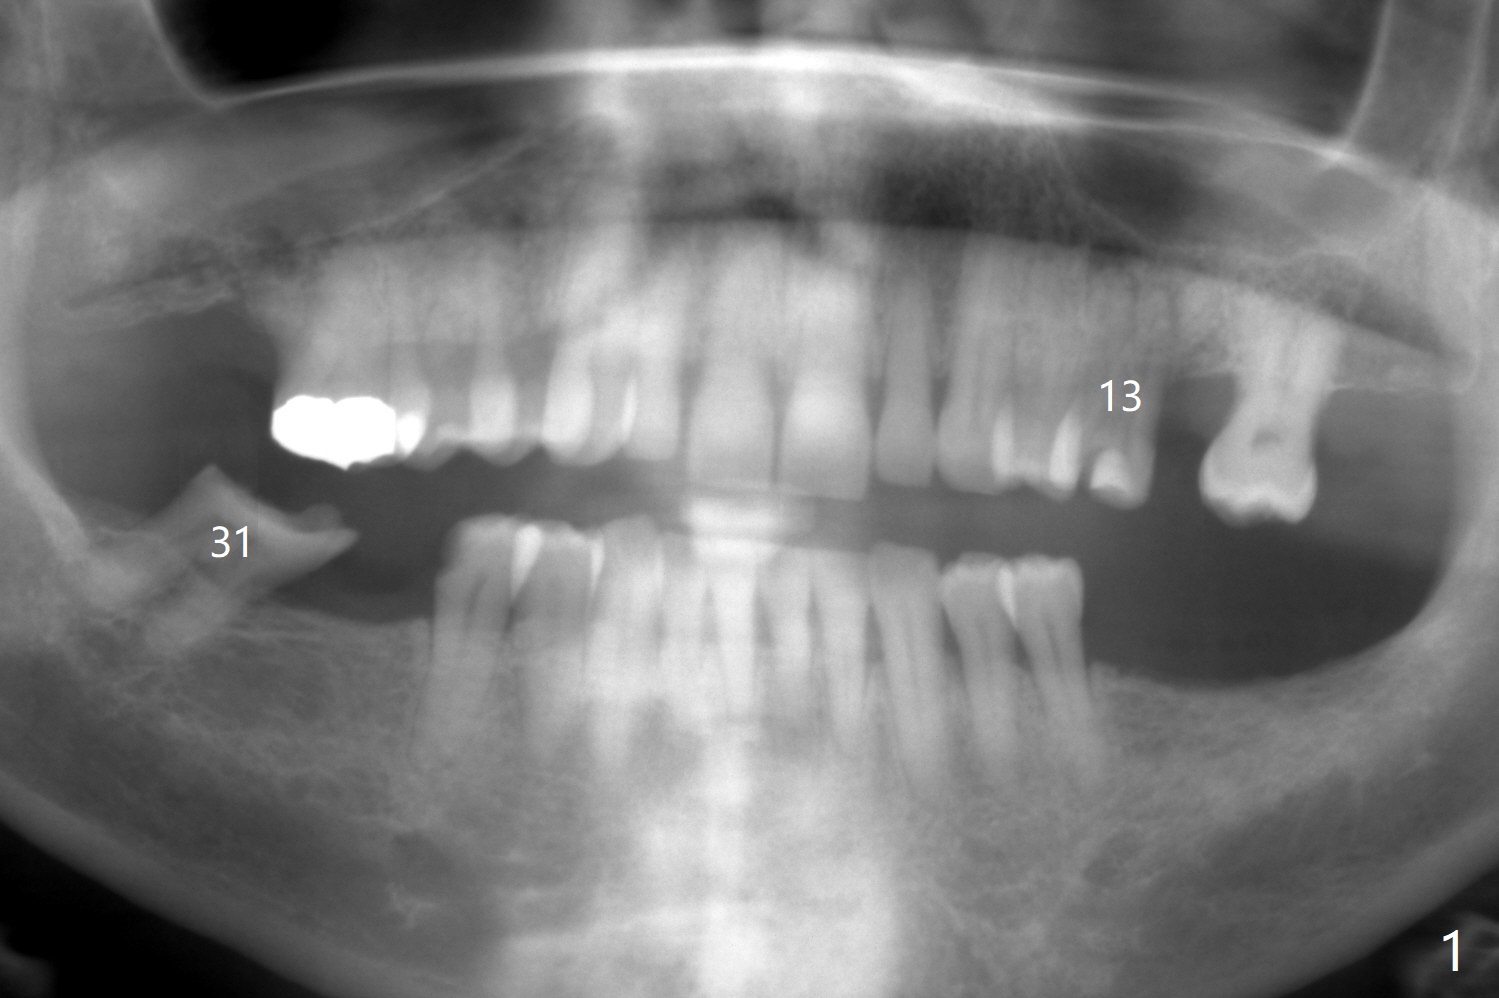

A 59-year-old woman has lost several teeth. The remaining ones are under stress (over-loaded), either severely worn (Fig.1 #31) or fractured (#13). The latter has 2 sockets with severe infection (Fig.2, IS implant). Start osteotomy in the palatal socket. Since the bone height is 11 mm (Fig.3), place PRF and bone graft before a 4x11 mm implant.